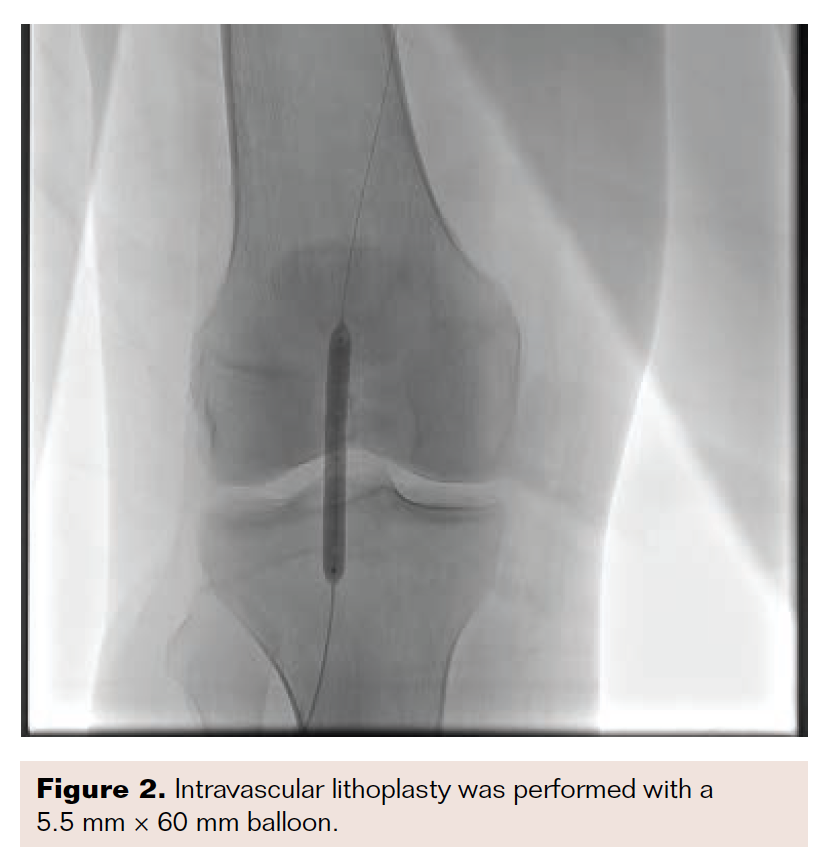

Intravascular lithotripsy is a new approach for controlling dissections, especially in severely calcified lesions. By creating ultrasonic waves, lithotripsy can effectively disrupt the sheets of calcium within plaque, and therefore improve the results of balloon angioplasty by minimizing both recoil and dissection, which are both more common in lesions with severe calcification.

I recently treated a patient with nonhealing ulceration of his right great toe. He had a severely calcified lesion in his popliteal artery, as demonstrated in Figure 1. Due to the calcification, I performed intravascular lithotripsy with a 5.5 mm × 60 mm balloon (Figure 2). After balloon inflation, the lesion had a residual type C dissection (Figure 3). Therefore, I placed 3 tack devices across the area of dissection (Figure 4). Final angiography demonstrated no residual dissection or recoil (Figure 5).